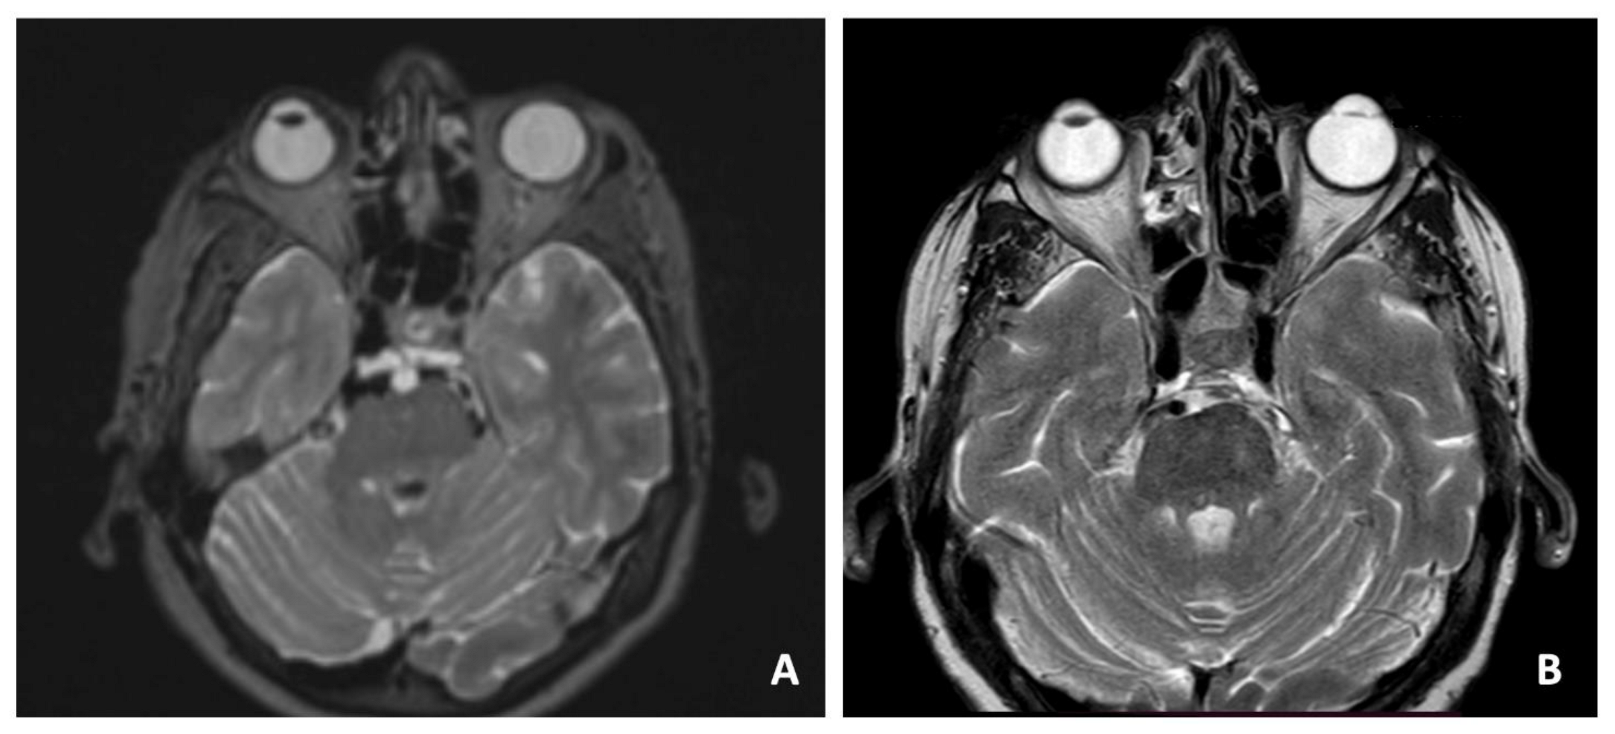

3.2. Case 2—Ecchordosis Physaliphora

| 2 | 69 | F | Cephalea, aqueous rhinorrhea | EEA | Resection and CSF leak repair | Ecchordosis physaliphora | None | None | 24 months | Alive without disease |